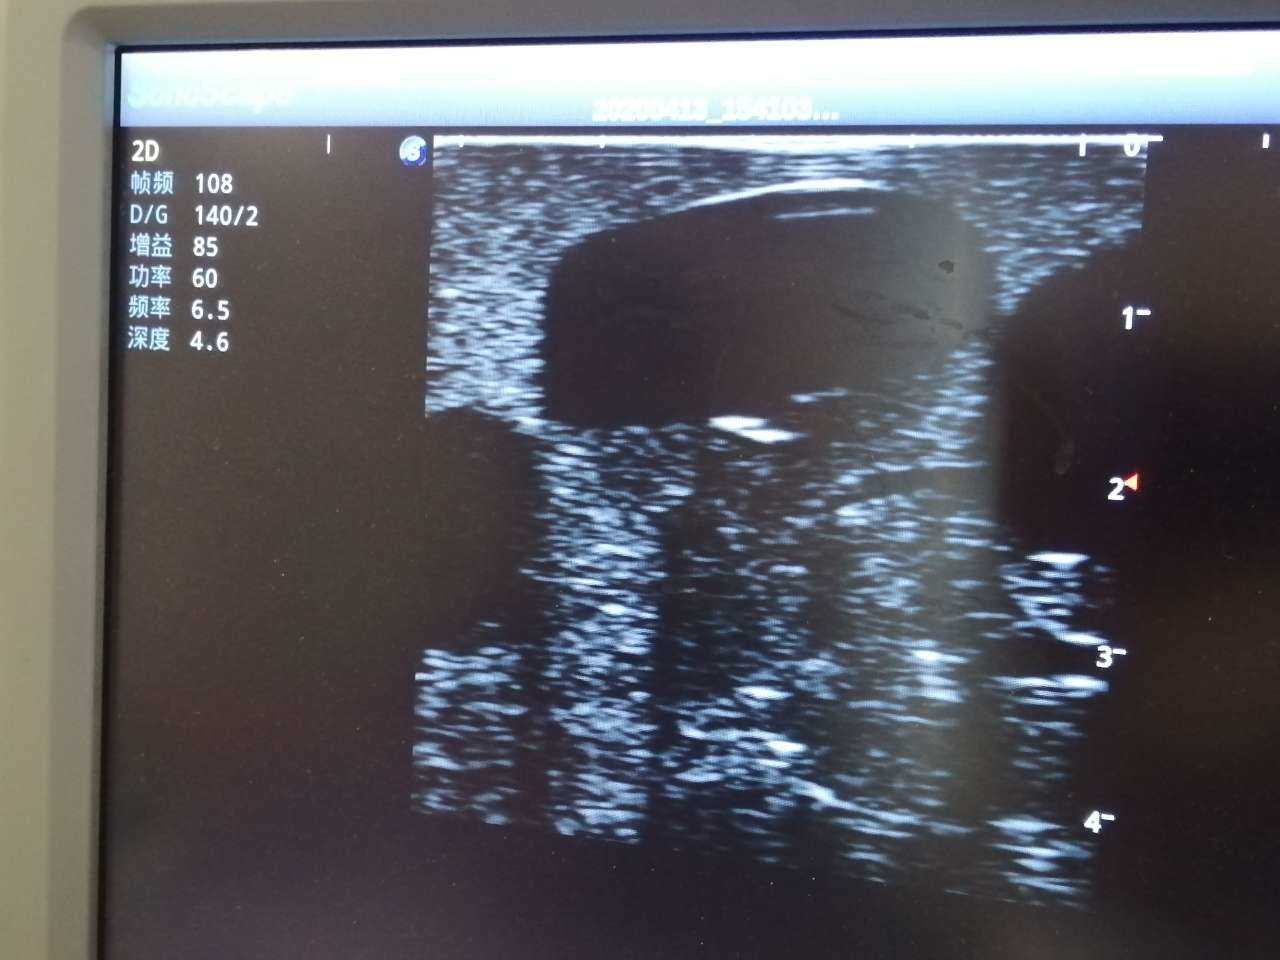

Abscess Drainage Ultrasound Trainer

Model TYE1562

Outline

The trainer is designed for abscess ultrasound recognition, drainage, surgical cutting & suturing. With realistic landmarks and high-quality images, it’s an excellent choice for abscess-related skill training and practice.

Skills Gained

· Proper transducer positioning

· Ultrasound image interpretation

· Ultrasound recognition of abscess

· Abscess drainage

Features

· Anatomy: accurate anatomical structures like iliac crest, cleft starting point etc.

· Different abscess types: single sac on the right side and multiple sacs on the left side

· Durable material, easy to carry

· Realistic abscess feel and touch

· Compatible with various real ultrasound machines

· High-quality ultrasound images to show skin, soft tissues, abscess cavity and pus

· Support abscess incision, drainage with visible fluid and suturing